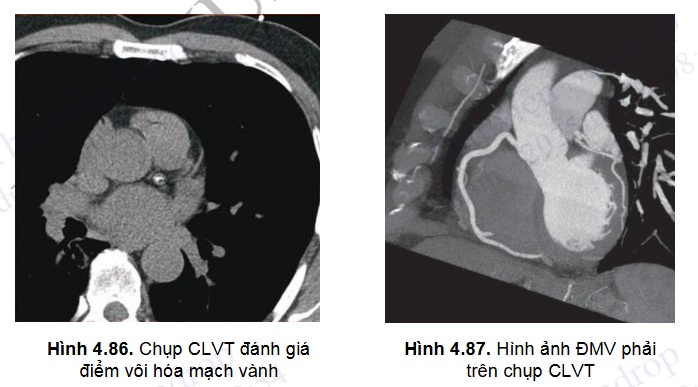

Hiện nay, công nghệ chụp cắt lớp vi tính không ngừng được phát triển cho phép thăm dò động mạch vành ở nhiều mức độ: đánh giá điểm vôi hóa của các mảng xơ vữa mạch vành, mức độ hẹp lòng mạch của động mạch vành tự nhiên và các đoạn cầu nối động mạch vành, kích thước và chức năng thất trái, giải phẫu hệ tĩnh mạch phổi và các cấu trúc tim khác.

- Chụp cắt lớp vi tính không cản quang đánh giá độ vôi hóa hệ động mạch vành.

- Chụp cắt lớp vi tính đa dãy có cản quang đánh giá cấu trúc và mức độ hẹp của hệ động mạch vành tự nhiên và các cầu nối động mạch vành.